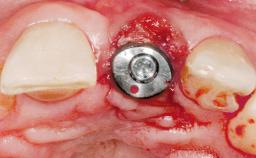

Late Placement of an Implant in a Maxillary Left Central Incisor Site

A 30-year-old female patient had lost tooth 21 and was referred to our clinic for consultation and treatment. Due to advanced apical infection, tooth 21 had been extracted two months earlier at another clinic and an acrylic-resin tooth had been bonded to the adjacent teeth. The patient desired implant treatment to avoid any damage to the adjacent natural teeth. While the patient had no history of any systemic disorder, she was a heavy smoker and exhibited medium to advanced periodontitis in the entire jaw. After the initial treatment to achieve a pocket probing depth of less than 4 mm and no bleeding on probing, a decrease in the height of the papillae mesial and distal to the extraction site and overall gingival recession were observed.

Bone Volume Deficient horizontally, requiring prior grafting